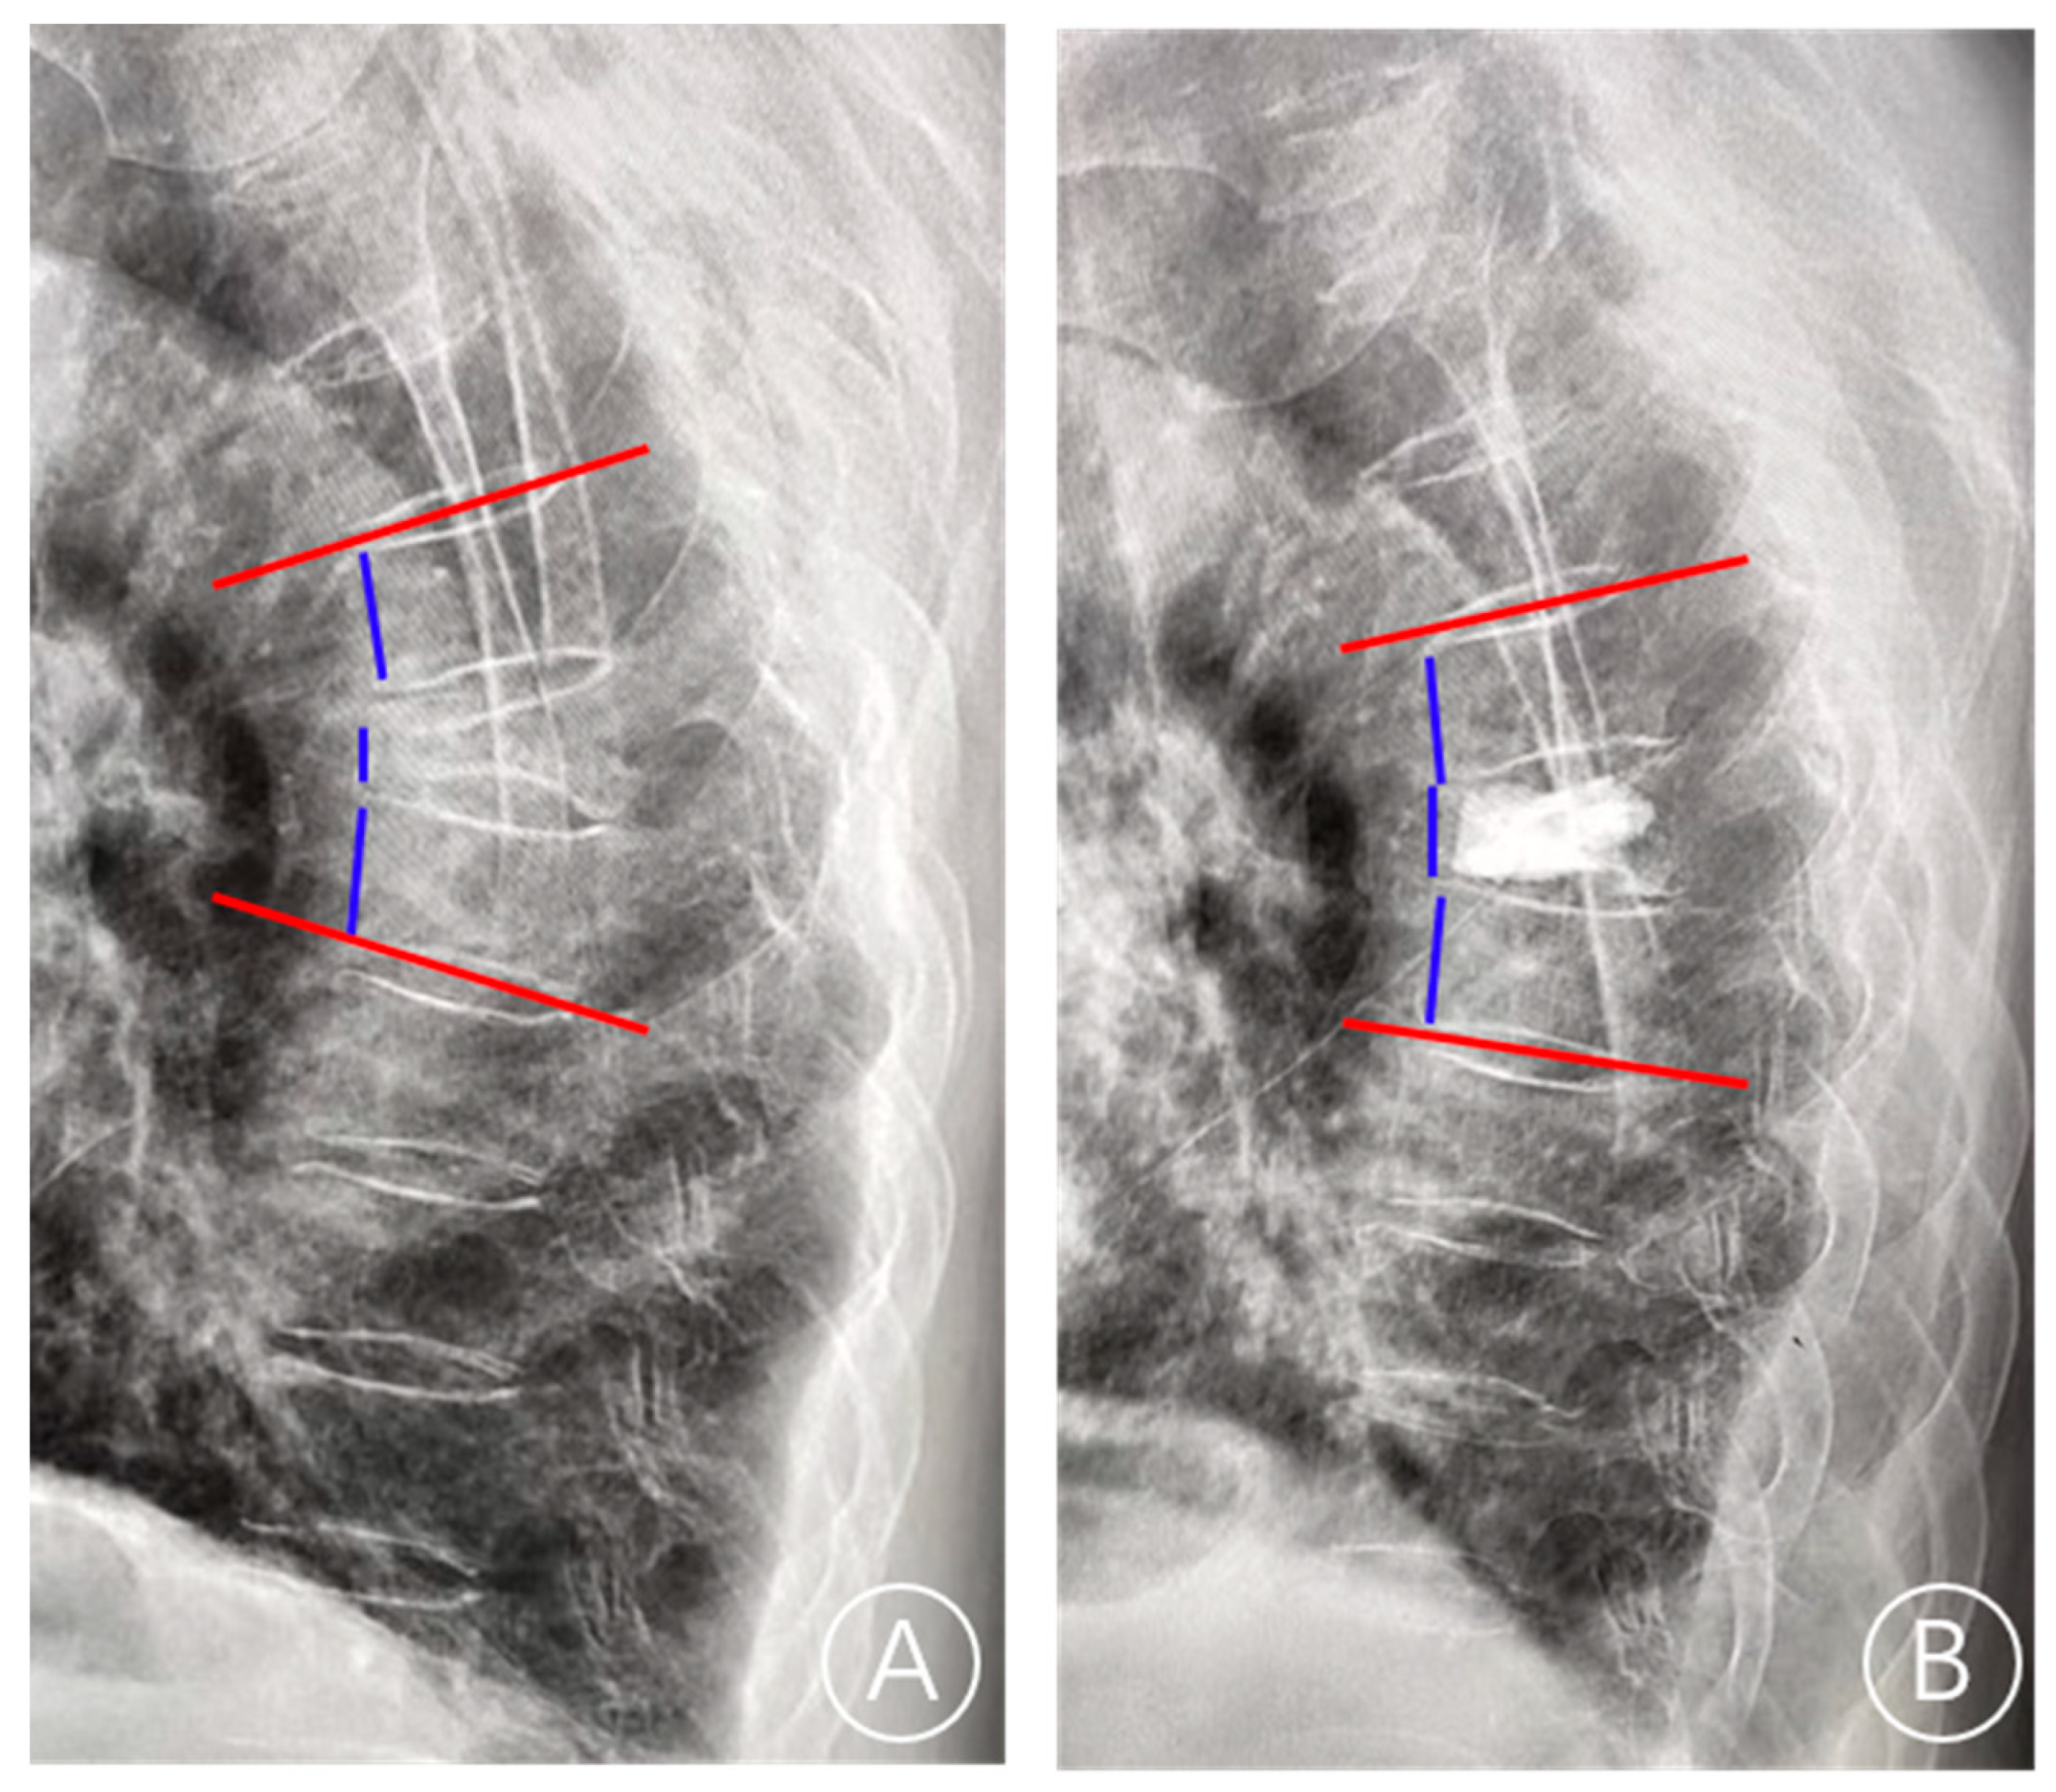

BMI (kg/m2) was calculated as weight (kg) divided by the height squared (m2). The thoracolumbar junction is defined as T11–L2. In terms of Kümmell’s disease staging, stage I: vertebral body height loss <20%, with or without adjacent intervertebral disc degeneration; and stage II: vertebral body height loss >20% along with adjacent disc degeneration. Cement leakage was defined by postoperative X-ray or CT examination showing that the bone cement exceeds the upper and lower endplates. The local Cobb angle was defined as the angle between the inferior endplate of the superior vertebra of the fractured vertebra and the superior endplate of the inferior vertebra of the fractured vertebra. The restoration rate of vertebral height was calculated as follows: (anterior height of fractured vertebra/([upper adjacent vertebral anterior height + lower adjacent vertebral anterior height]/2)). The local restoration of the Cobb angle was calculated as follows: ((preoperative Cobb angle—postoperative Cobb angle)/preoperative Cobb angle) [13] (Figure 3). The even cement distribution is characterized by the spongiform dispersive bone cement in contact with the upper and lower endplates.

Figure 3.

The lateral radiograph showed the measurement of the anterior vertebral height and the local Cobb angle. (A) On the preoperative lateral radiographs, the anterior height of the fractured vertebra, the upper adjacent vertebral anterior height, the lower adjacent vertebral anterior height, and the Cobb angle were measured. (B) On the postoperative lateral radiographs, the anterior height of the fractured vertebra, the upper adjacent vertebral anterior height, the lower adjacent vertebral anterior height, and the Cobb angle were measured. The red line is the endplate and the blue line is the anterior vertebral height.